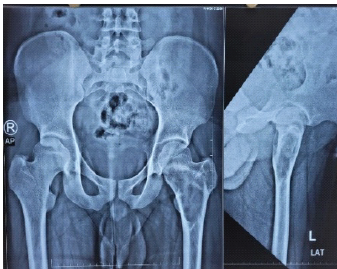

Assessing the Importance of Anteromedial Cortical Support in Fixing Pertrochanteric Fractures: A Comprehensive Study

Makesh Ram Sriraghavan , Manar Moideen , Manivelan Dhamotharan , Poornima Kumararaja

………………………………p.255-261